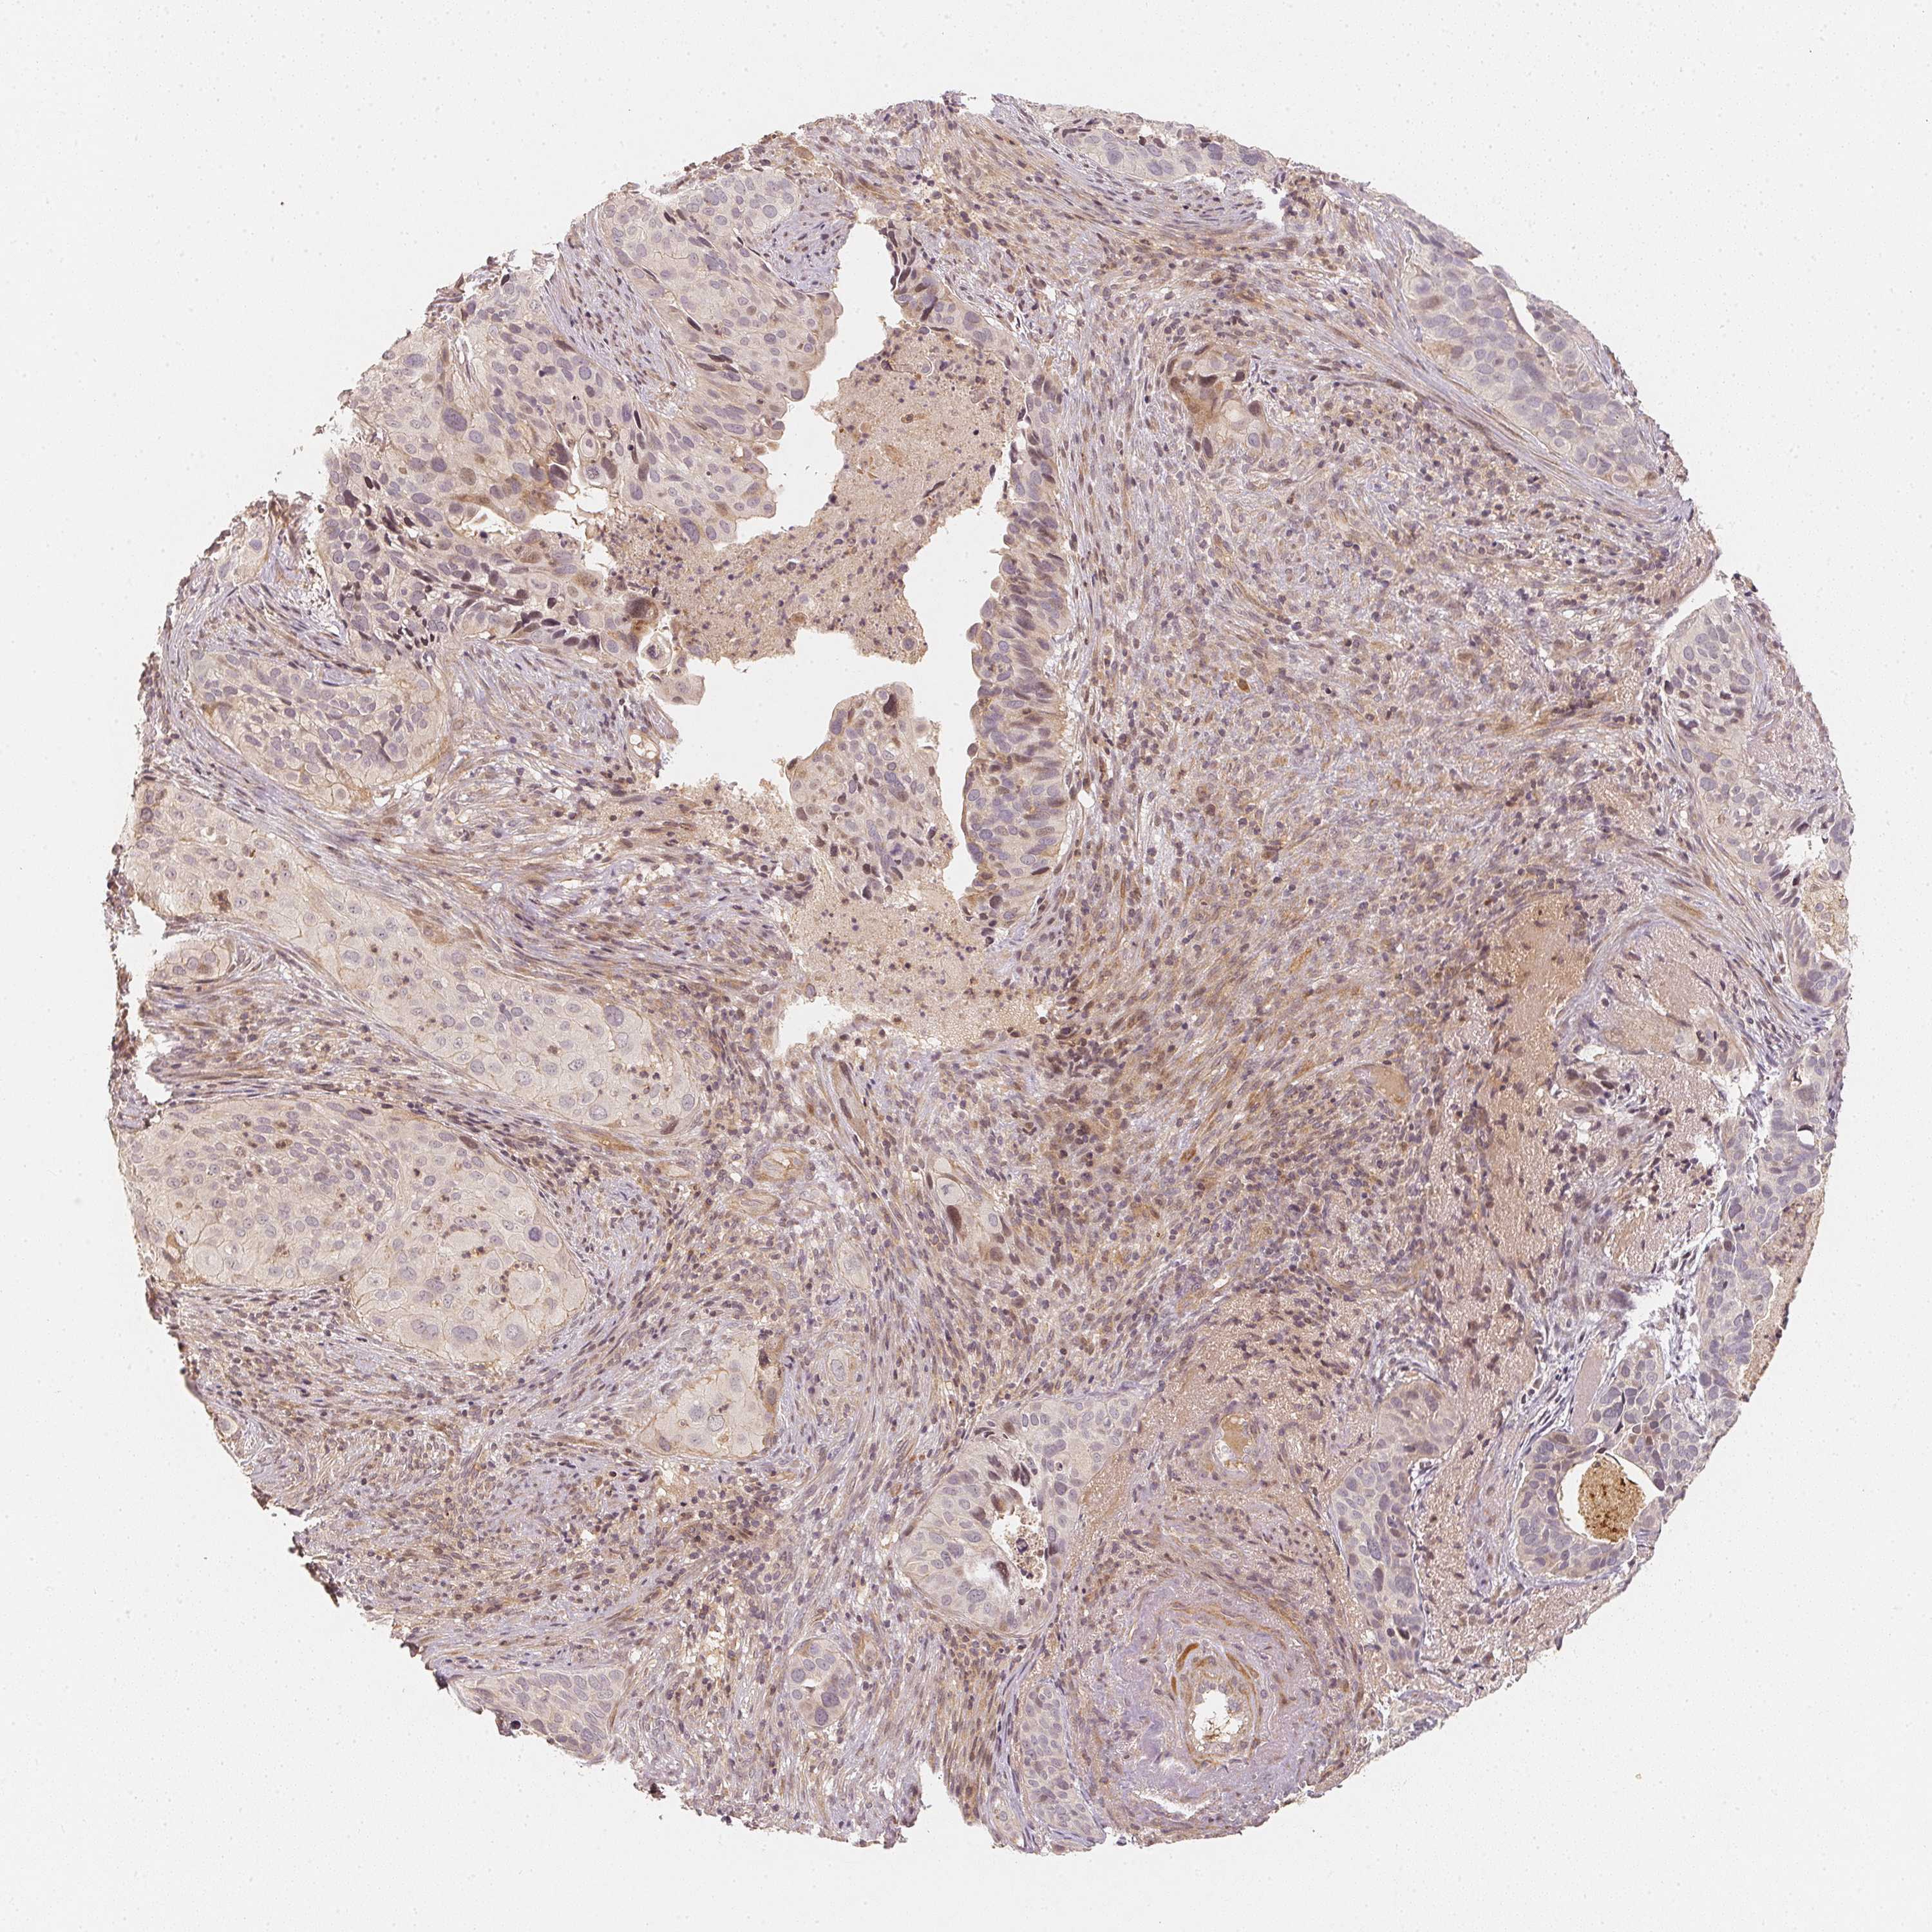

CERVICAL CANCER - Protein expressioni

A mouse-over function shows sample information and annotation data. Click on an image to view it in a full screen mode. Samples can be filtered based on level of antibody staining by selecting one or several of the following categories: high, medium, low and not detected. The assay and annotation is described here.

Note that samples used for immunohistochemistry by the Human Protein Atlas do not correspond to samples in the TCGA dataset.

Antibody stainingi

Antibody staining in the annotated cell types in the current human tissue is reported as not detected, low, medium, or high, based on conventional immunohistochemistry profiling in selected tissues. This score is based on the combination of the staining intensity and fraction of stained cells.

Each image is clickable and will lead to virtual microscopy that enables deeper exploration of all samples and also displays staining intensity scores, fraction scores and subcellular localization as well as patient and tissue information for each sample.

Antibody CAB068501

Staining

High

Medium

Low

Not detected

Intensity

Strong

Moderate

Weak

Negative

Quantity

>75%

75%-25%

<25%

None

Location

Nuclear

Cytoplasmic/membranous

Cytoplasmic/membranous,nuclear

Squamous cell carcinoma, NOS

Adenocarcinoma, NOS